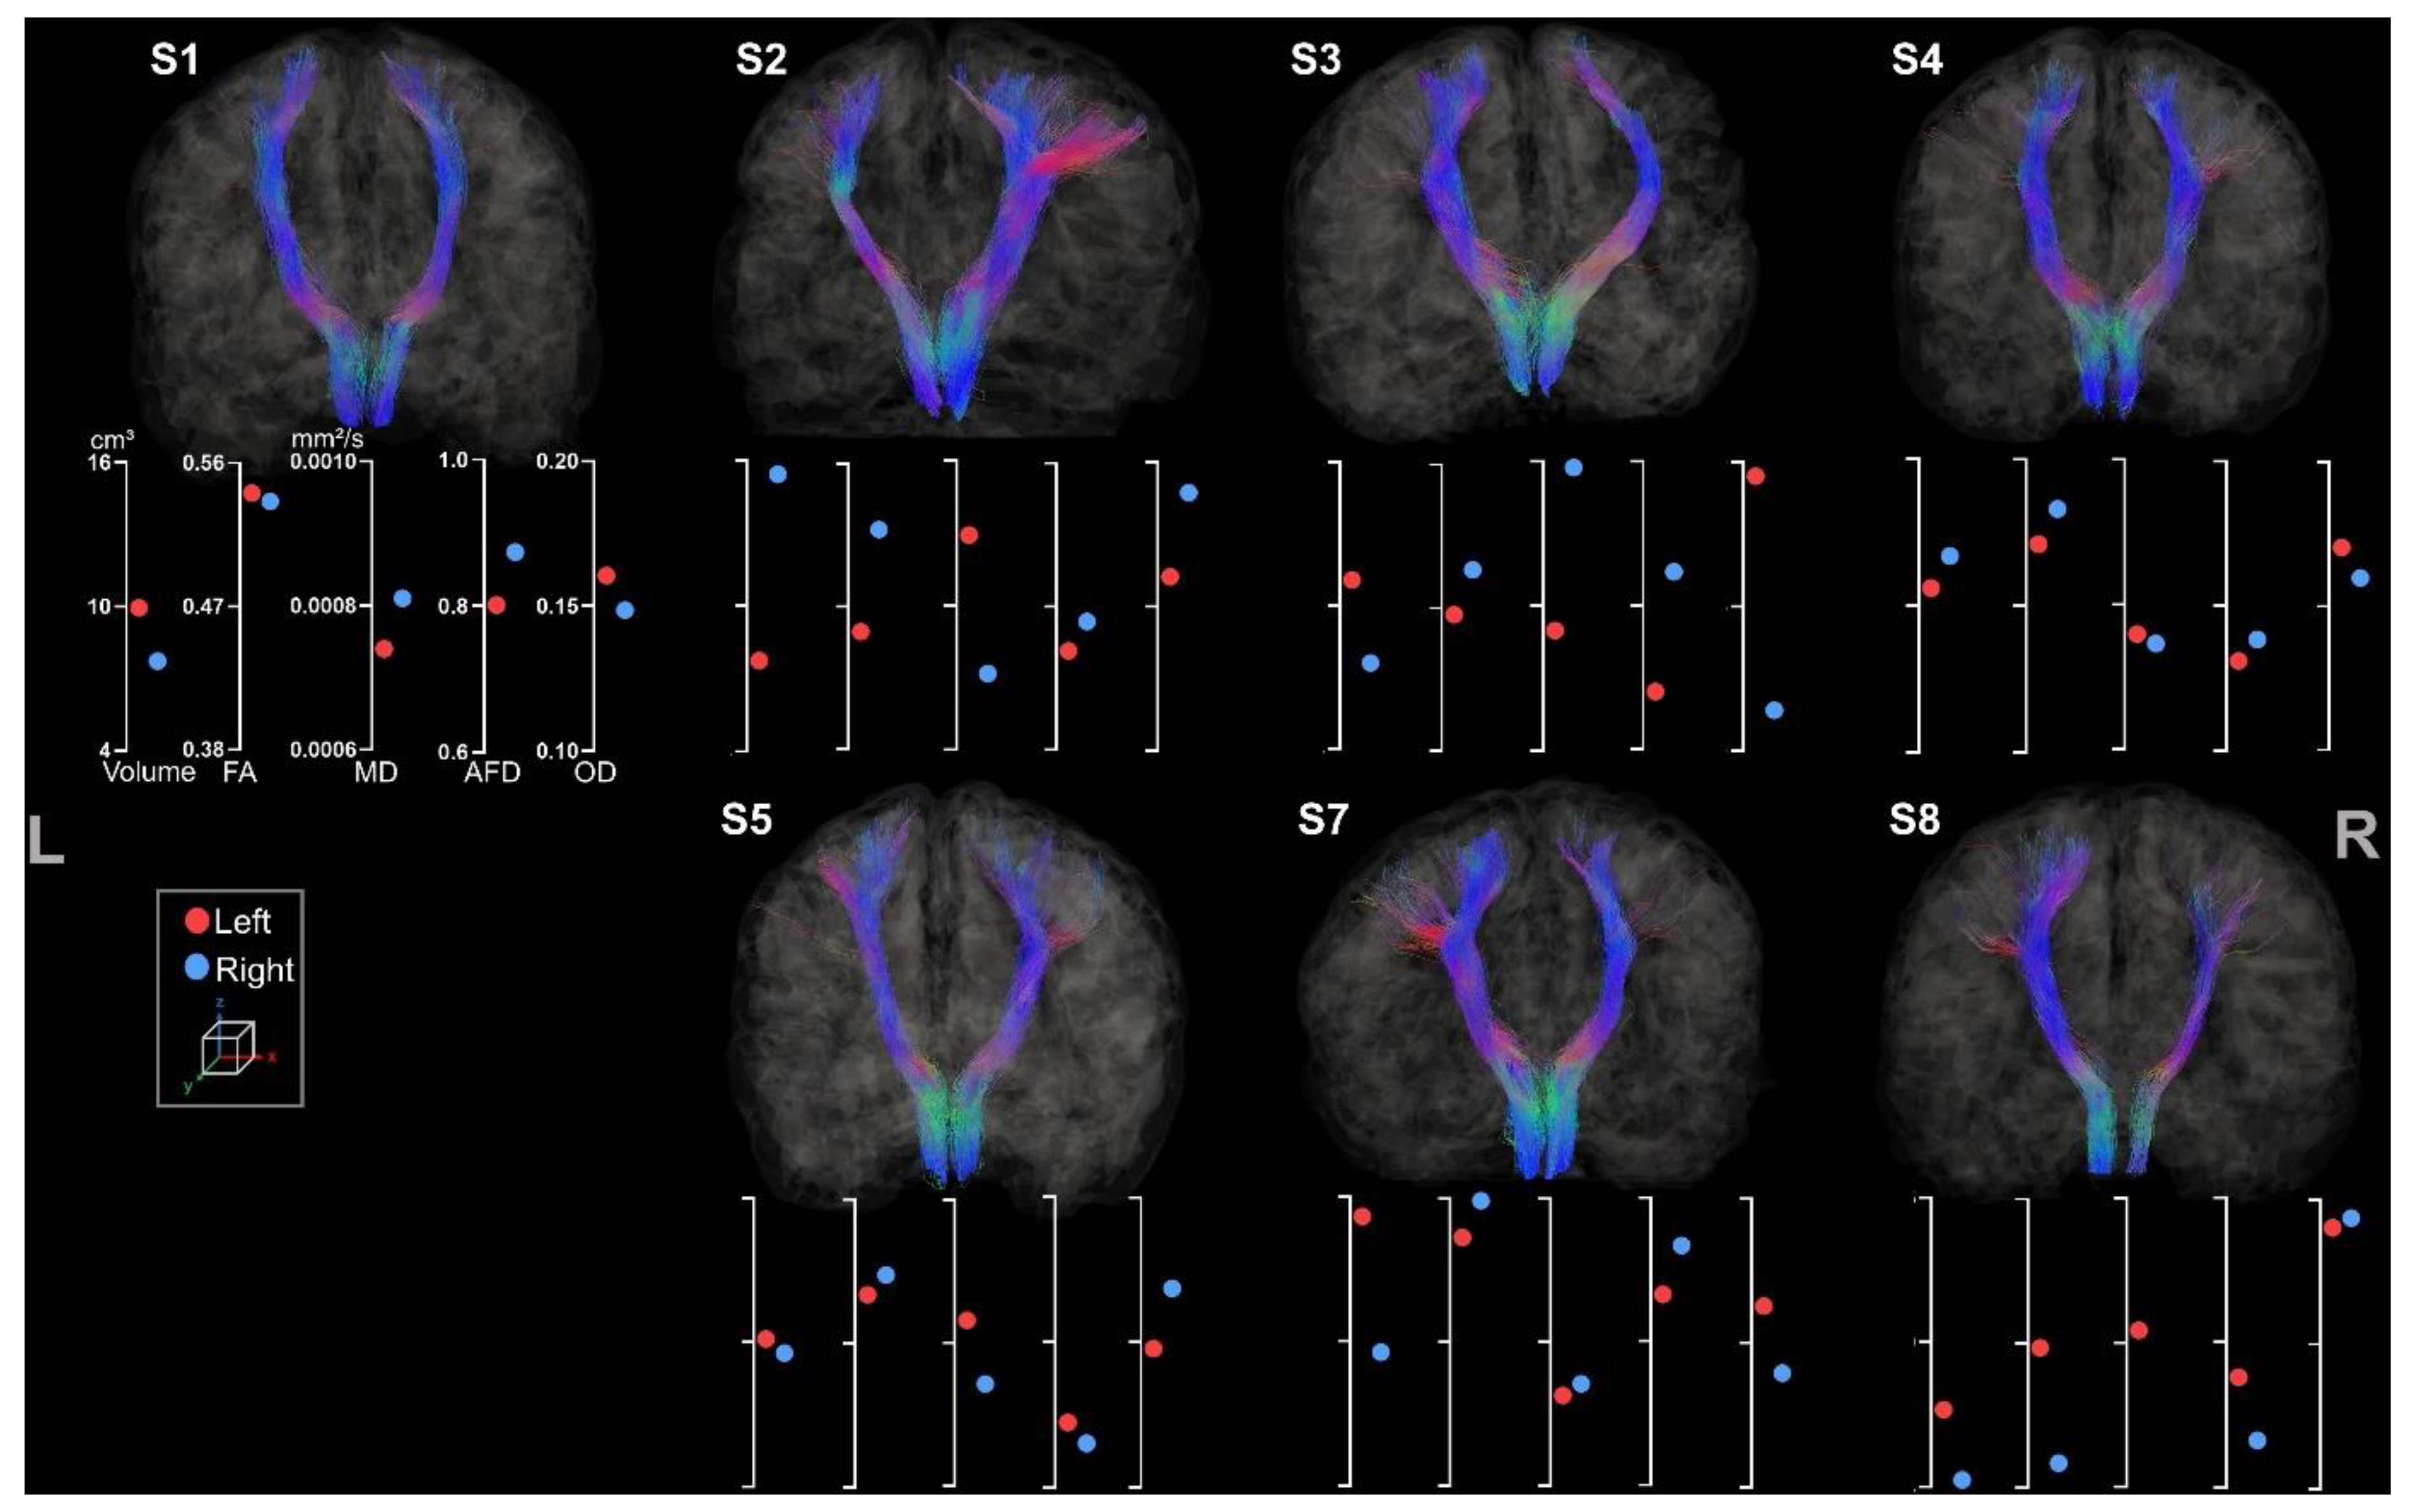

3.2.1. Corticospinal Tracts

3.2.2. Corpus Callosum